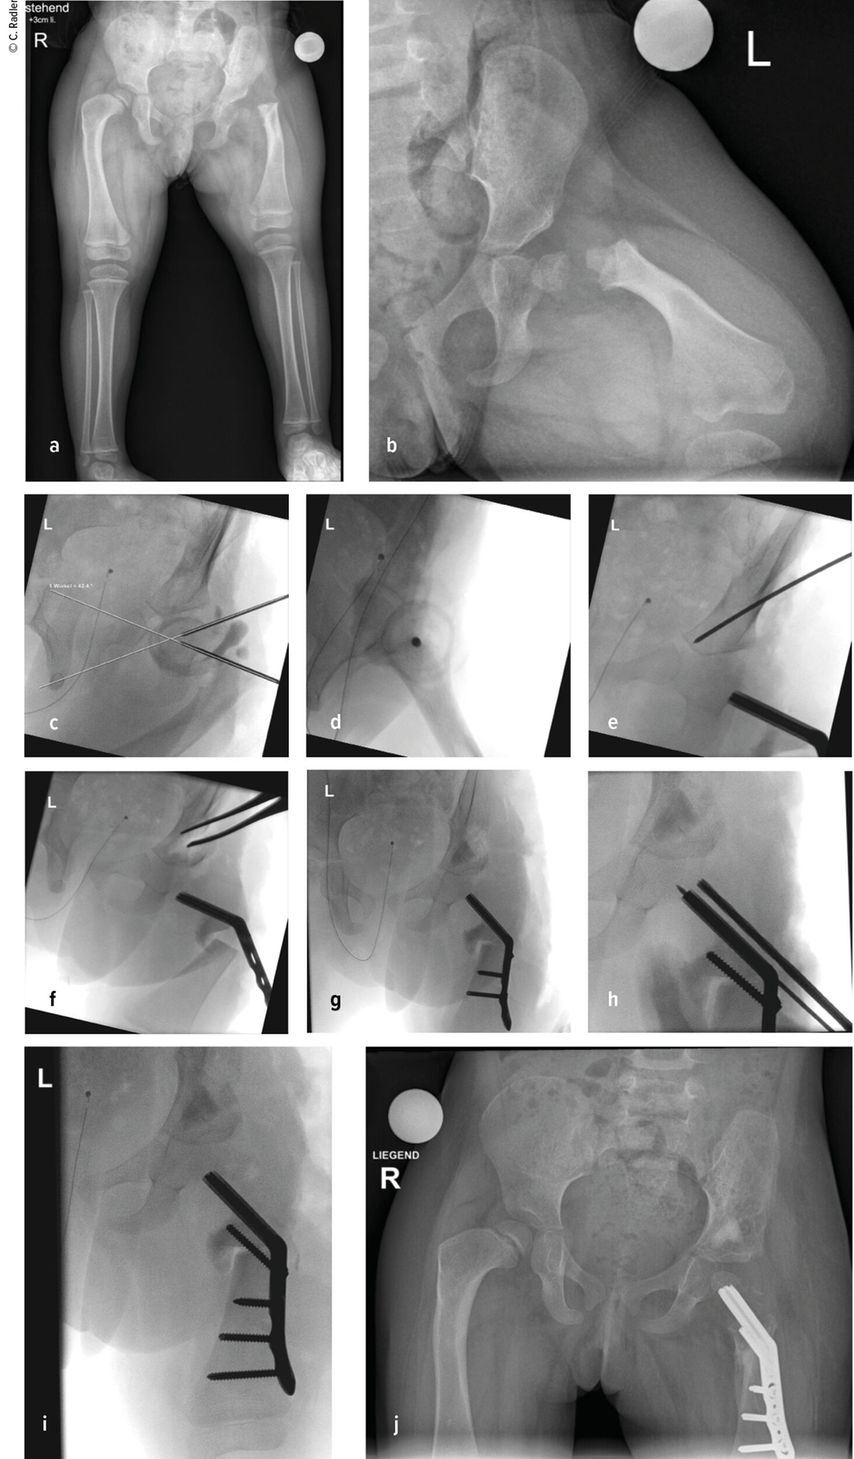

Die Valgusstellung kann sehr einfach über eine Wachstumslenkung (Hemiepiphysiodese mit 2-Loch-Platte) korrigiert werden. Um eine Subluxation am Kniegelenk zu verhindern, muss bei allen diesen Fällen bei Verlängerung mit Fixateur dieser knieüberbrückend montiert werden (Abb.4). Bei Verlängerung über einen Verlängerungsmarknagel wird in diesen Fällen eine Oberunterschenkelschiene (KAFO) verwendet und prophylaktisch, soweit noch vorhanden, die Fascia lata auf Höhe des oberen Patellapols durchtrennt. Bei deutlicher Instabilität oder auch Subluxation ist eine Stabilisierung über eine komplexe Operation, die als Super-Knee-Operation subsumiert wird, erforderlich.2 Diese Operation kann auch an die Hüftrekonstruktion/Super-Hip-Operation angeschlossen werden, da hier die Faszie ohnehin präpariert wird. Je nach Alter des Patienten und dem Ausmaß der Instabilität wird hierbei die Fascia lata nach Präparation bis an das Tuberculum Gerdyi und Halbieren der Länge nach entweder extraartikulär oder intraartikulär geführt. Auch die Fixation wird abhängig vom Alter mit Biotenodeseschrauben oder Weichteilzügelung durchgeführt.

Abb. 4: Platzierung (a–d) eines Fixateur externe mit Knie-Überbau (e–g) zum Schutz vor (Sub-)Luxation